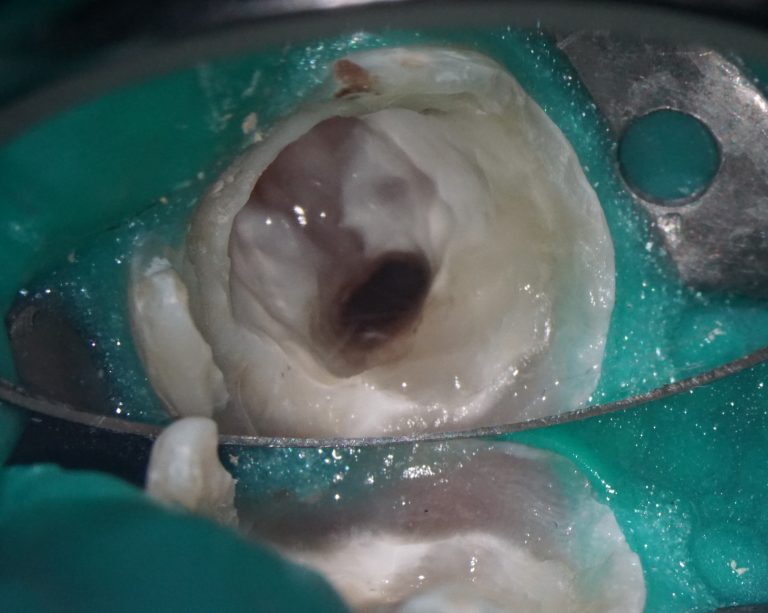

The patient came with complaints that his dental crown on tooth 25 (Universal 13) fell out